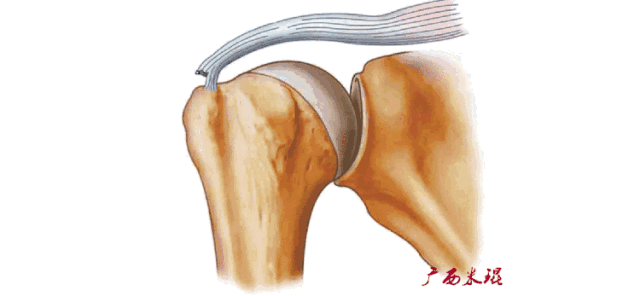

1、肩峰撞击

肩峰撞击由Neer于1972年提出,肩峰下关节由于解剖结构原因或动力学原因,在肩的上举、外展活动中,因肩峰下组织发生撞击而产生的症状。肩峰撞击与肩袖损伤互为因果,是肩关节MRI诊断的重中之重!

肩峰撞击并非仅指肩峰,撞击部位可以在肩峰前1/3前下面、喙肩弓、肩锁关节下面以及喙突,对应面是大结节、小结节,MRI阅片中要重点关注这些结果以及夹于其中的肩袖组织。